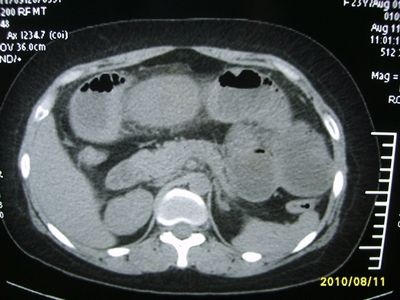

5天前突发腹痛剧烈难忍,伴解淡血水样便。近一天来腹痛缓解,没有明显的腹膜炎的体征。今天照的腹部ct。从ct上看感觉是一个绞窄性肠梗阻,但是现在没有腹痛。不好解释

要有麻烦了,感觉小肠有套叠还有扭转改变,估计部分已有坏死。

高位肠梗阻(不全性),原因小肠(空肠)扭转,肠壁水肿增厚,成年人肠梗阻要排除合并占位,建议手术。

绞窄性肠梗阻_肠管套叠 扭转,肠壁明显水肿。

病人现在没有腹痛。怪了。从影像上来看。确实是绞窄了。但是没有腹痛。没有明显的腹膜炎的体征。确实有不好解释。难道是坏死了。反而不痛了。怪怪怪

支持绞窄性肠梗阻,肠壁明显水肿并见有多发小泡状积气--肠坏死

考虑绞窄性肠梗阻并肠坏死。